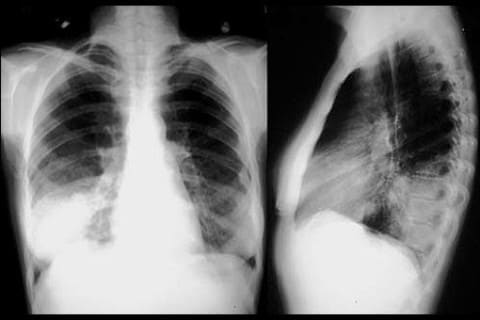

Острая пневмония. Одной из частых причин воспаления легких у детей является гемофильная палочка. Пневмония может быть очаговой или крупозной (с поражением доли легкого или нескольких долей), часто осложняется плевритом (воспаление плевры – оболочки легкого) – до 70% случаев у детей. У пациента высокая температура, слабость, вялость, кашель сначала сухой или малопродуктивный, а затем становится влажным (мокрота гнойная с желтоватым оттенком). Нередко нарушения дыхательной экскурсии, что проявляется одышкой. Течение пневмонии затяжное, трудно поддается лечению, может быть волнообразным.

Гемофильная пневмония